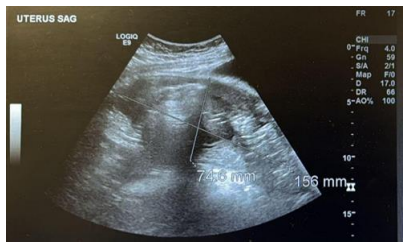

Further evaluation with MRI of the pelvis confirmed a grossly abnormal uterus containing a fluid-fluid and fluid-air level measuring 10 × 9 × 6 cm. Restricted diffusion was observed in the most posterior portion of the endometrial fluid collection, strongly indicating the presence of pus. An adjacent vaginal collection, measuring 10 × 9 × 8 cm, was also identified, but it did not show restricted diffusion, likely representing the prolapsed and necrotic portion of the fibroid (Figure 2 and 3 ). These findings were highly indicative of pyomyoma, necessitating immediate surgical intervention.

Figure 2 Pelvic MRI Sagittal view